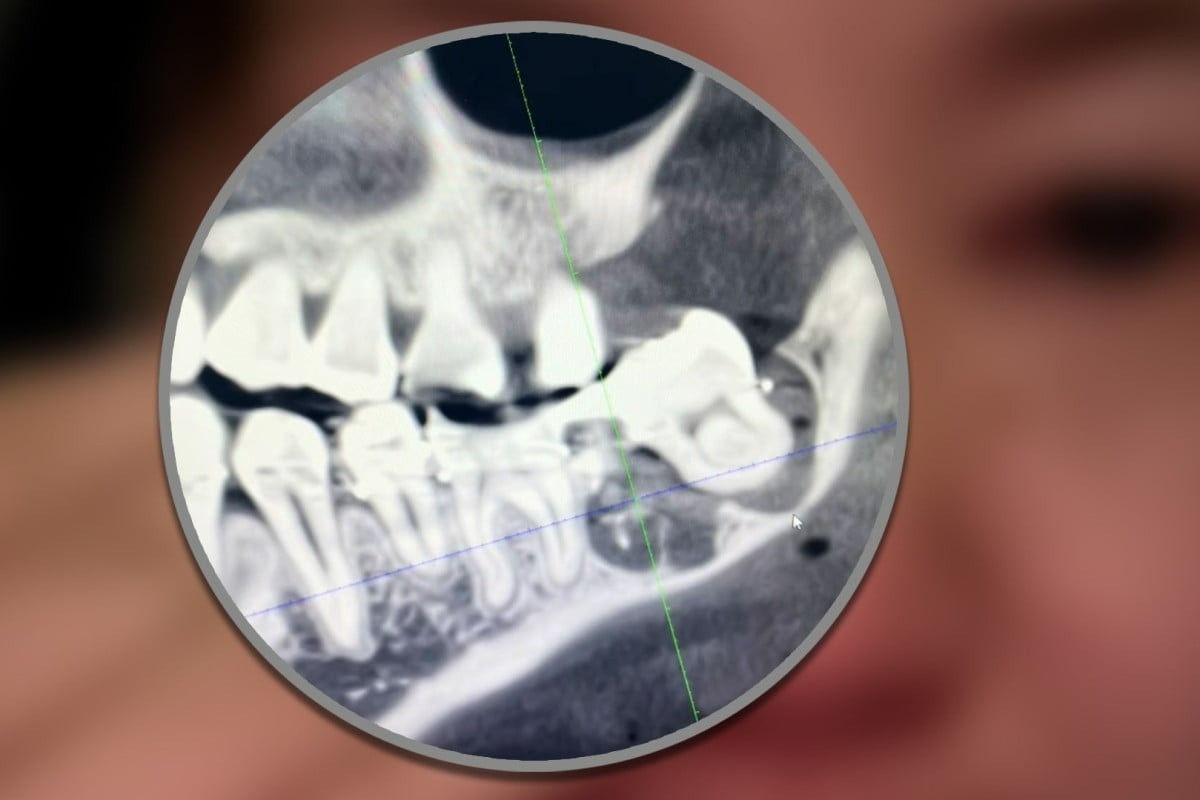

Tuy nhiên, trong quá trình phẫu thuật, các bác sĩ tại bệnh viện đã nhổ nhầm một chiếc răng khỏe mạnh thay vì chiếc răng khôn cần thiết. Khi phát hiện sai sót, thay vì xử lý đúng cách, các bác sĩ lại cố gắng đưa chiếc răng bị nhổ nhầm trở lại bằng cách buộc nó vào một số chiếc răng khác bằng dây thép.

Một nha sĩ không liên quan đến sự cố này cho biết, việc nhổ nhầm răng là một lỗi trong đánh giá của bác sĩ, điều này rất hiếm khi xảy ra và được coi là một sự cố y tế. Luật sư Zhu Xue từ Công ty Luật Celue Bắc Kinh cho biết nếu bác sĩ bị phát hiện chịu trách nhiệm về sự cố y tế này, bệnh viện sẽ phải chịu trách nhiệm bồi thường dân sự và có thể đối mặt với các hình phạt hành chính.